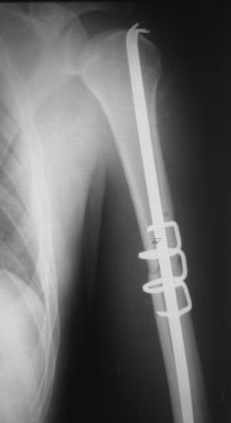

Добрый вечер!

Приложение как пример.

Что иллюстрирует этот пример? Это была множественная травма? Если это был изолированный перелом, то "золотой стандарт" - консервативное лечение.

Консервативно он уже лечился до этой операции в течение трёх с половиной месяцев.

А именно такой вариант операции выбран из экономических соображений.

вообще, торчашие в субакромиальное пространство шипы оставляют неизгладимое впечатление. Не думаю, что таким имплантом есть смысл гордиться